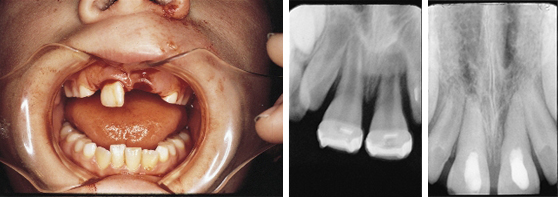

- For complicated cases involving traumatic injury and other instances where extended calcium hydroxide therapy is indicated.

- Treats periapical lesions, abscesses, traumatic injuries, root resorption, root perforations, and weeping canals

- Stimulates apexification and apexogenesis